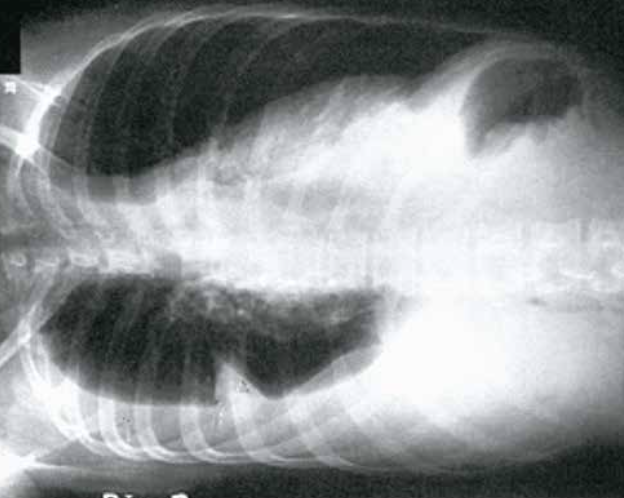

69

Neumoperitoneo. El neumoperitoneo es fácilmente detectable en la radiografía de tórax, incluso volúmenes de aire muy pequeños. En bipedestación aparece como una burbuja de aire libre bajo un hemidiafragma. Se apreciará una media luna de aire entre el diafragma y el hígado, en el lado derecho, o la burbuja gástrica en el izquierdo (y por tanto permite ver la pared gástrica en su borde superior).

70

Neumoperitoneo. El neumoperitoneo indica siempre una urgencia quirúrgica (perforación de víscera abdominal), excepto cuando se observa en los 3 días siguientes a una laparotomía, donde puede ser esperable. Recuerda que la mejor proyección para detectar neumoperitoneo es la PA de tórax.